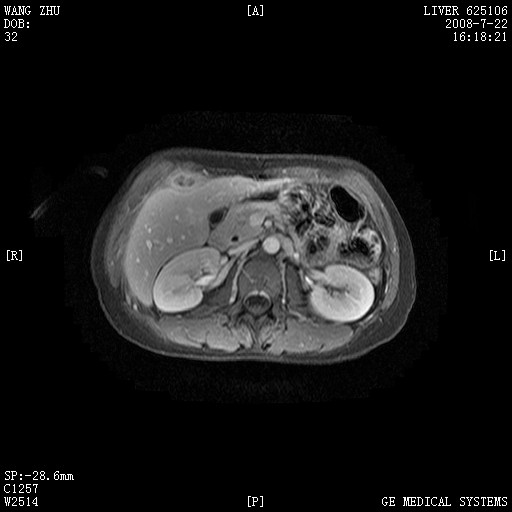

图像有点乱,病灶边缘清楚,可见纤维囊壁,灶旁可见异常灌注,增强显著增强,病灶有早期完全充填,无快退征像,考虑炎性病灶,肝结核可能性大,不知有何病史

肝前外缘见一类圆形囊性病灶,边缘强化,灶周肝为炎性渗出改变,其肝周可见少量腹水,符合炎性病变,病史较长---考虑腹膜结核。肝为外压性改变,脾为动脉期改变。